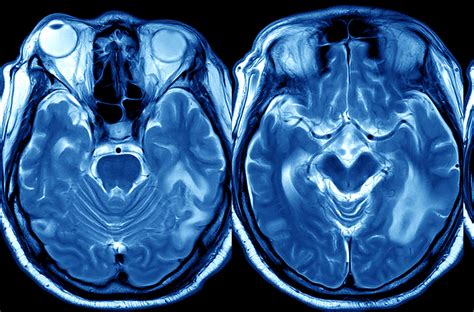

Esami di imaging come la TAC o la Risonanza Magnetica dell'encefalo sono fondamentali per evidenziare atrofia cerebrale (inizialmente a livello temporale mesiale/ippocampale nella MA amnesica, poi diffusa) o esiti vascolari. Esami "funzionali", come la PET con glucosio marcato, rilevano le aree cerebrali con minore attività metabolica.